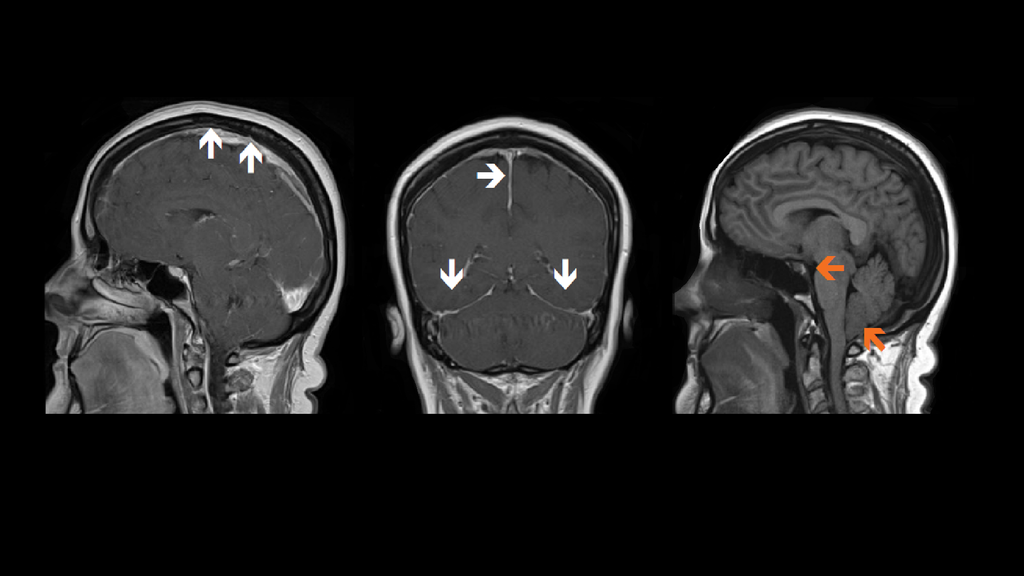

Spontaneous CSF Leaks Neurologic Clinics

From www.neurologic.theclinics.com

Spontaneous CSF Leaks Neurologic Clinics Can You Work With Csf Leak yes, csf leaks can be dangerous if left untreated and the leak is especially fast or large; many people experiencing intracranial hypotension due to a spinal cerebrospinal fluid (csf) leak find physical activity challenging due to their. a csf leak occurs when cerebrospinal fluid (csf) escapes from the protective layer surrounding the brain and spinal cord. This. Can You Work With Csf Leak.